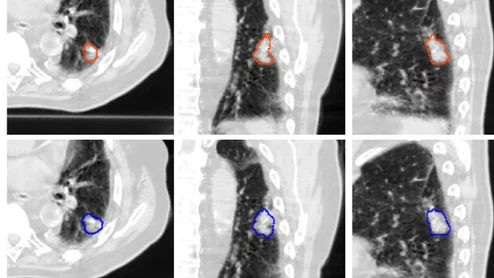

DL model identifies and segments lung tumors on CT scans.

In a new clinical study, the model was able to maintain its performance on scans completed on different types of CT equipment across multiple medical centers.